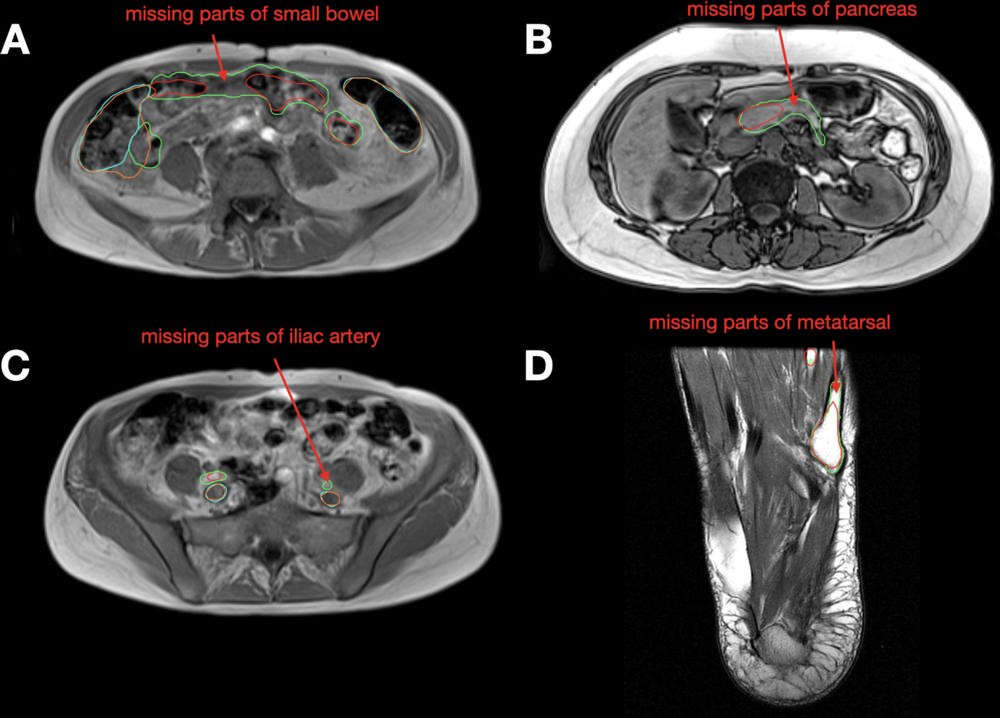

Figure 6. Examples of failure cases on axial MRI scans from the MRI test set. (A) The small bowel model prediction (red) is missing parts compared with the reference segmentation (green). The colon prediction (orange) overreaches the reference segmentation (cyan). (B) The pancreas model prediction (red) is missing parts compared with the reference segmentation (green). (C) The iliac artery prediction (red) is missing parts compared with the reference segmentation (green). The iliac vein prediction (orange) is very similar to the reference segmentation (cyan). (D) The metatarsal model prediction (red) is missing parts compared with the reference segmentation (green).